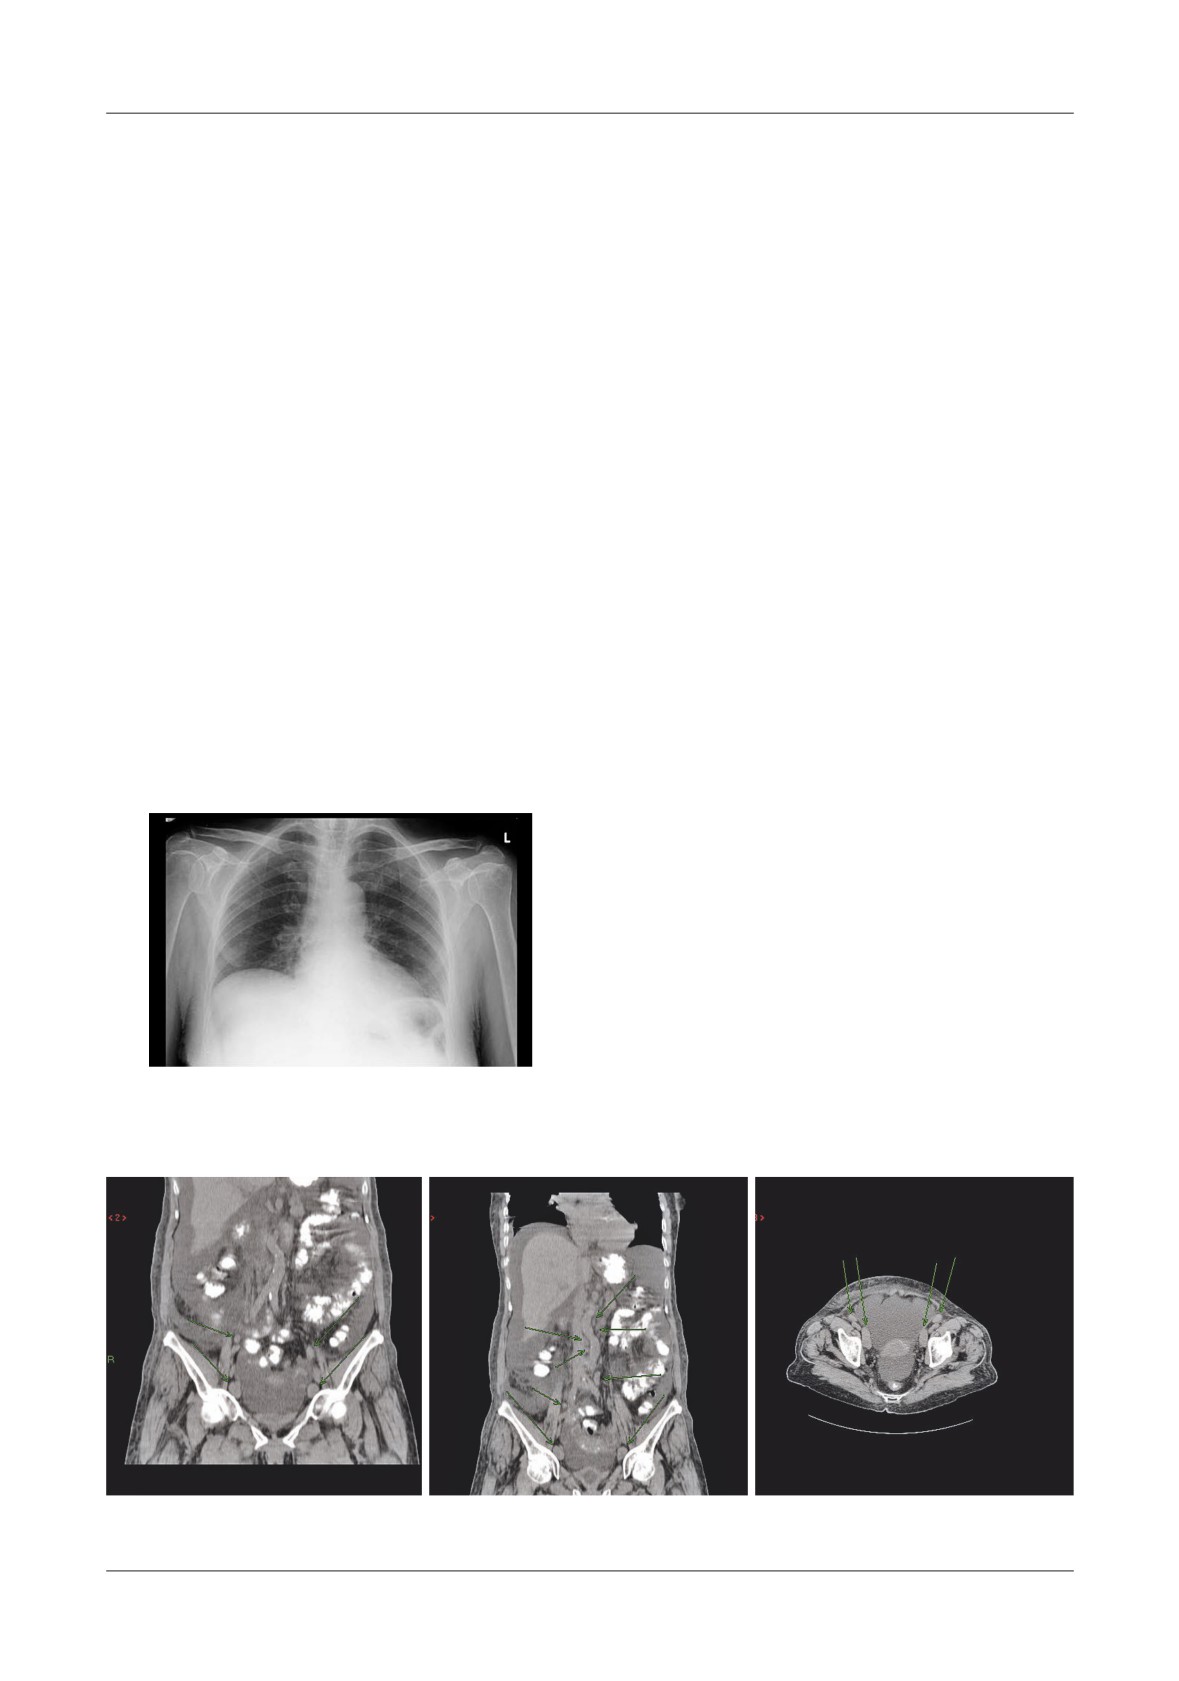

Figure 1. Pancreatic necrosis with the development of a pseudocyst, ileus and colonic in ltration in a 38

-year-old man. A-At admission the CT- shows enlarged pancreas and peripancreatic in ammation,  uid

(N=necrosis, P=pancreas, S=stomach), B-Lique ed necrosis nine days later with partially encapsulated

uid collection in the lesser sac, C-Dilated small bowel loops, with a haustral transverse colon. S=small

bowel, T=transverse colon, D-Five weeks later, fully encapsulated pseudocyst in the lower sac, with

lique ed necrosis in the neck of the pancreas (D=duodenum, N=necrosis, P=pseudocyst, S=stomach)

Figure 4. Pancreatic pseudocyst secondary to necrosis.

A - Liquefaction necrosis in the tail, B - Large pseudocyst bulging into the stomach

Figure 5. Pseudocyst communicating with  the pancreatic duct, A-With CT image of enlarged gland

and peripancreatitis, B-After discharge from hospital, 2 weeks later, CT shows a residual collection,

C-6 months later, the patient had abdominal pain, CT shows an enlarging pseudocyst,

D-Trans gastric punction with  stulography, shows communication with the Wirsung duct

pseudo cysts <5cm in size seen in asymptomatic patients

Most of the serious complications (4 cases), had the

at  the  end  of  an  acute  episode,  were  managed

tendency to occur predominantly late within a few

conservatively with CT- follow up control (Figure 5).